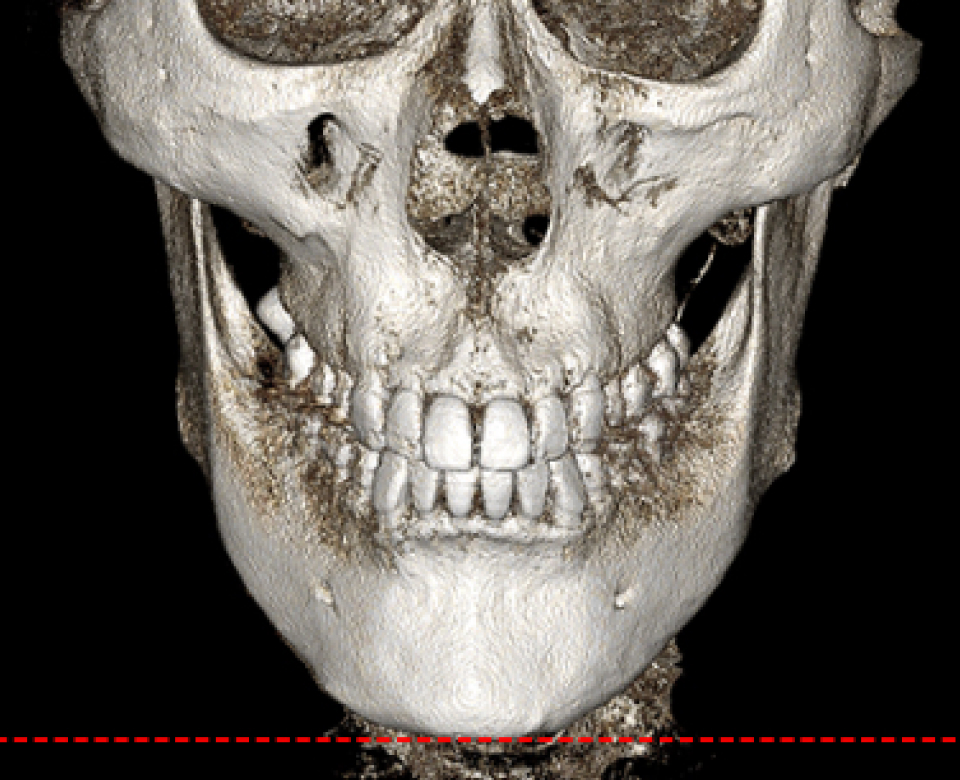

수술 전 3D-CT를 통해 신경의 위치를

1mm까지 분석하고,

원장님이 직접 수술 경로를 디자인하여

신경 손상을 원천 차단합니다

* 수술전 원장님이 직접 디자인한 사진입니다